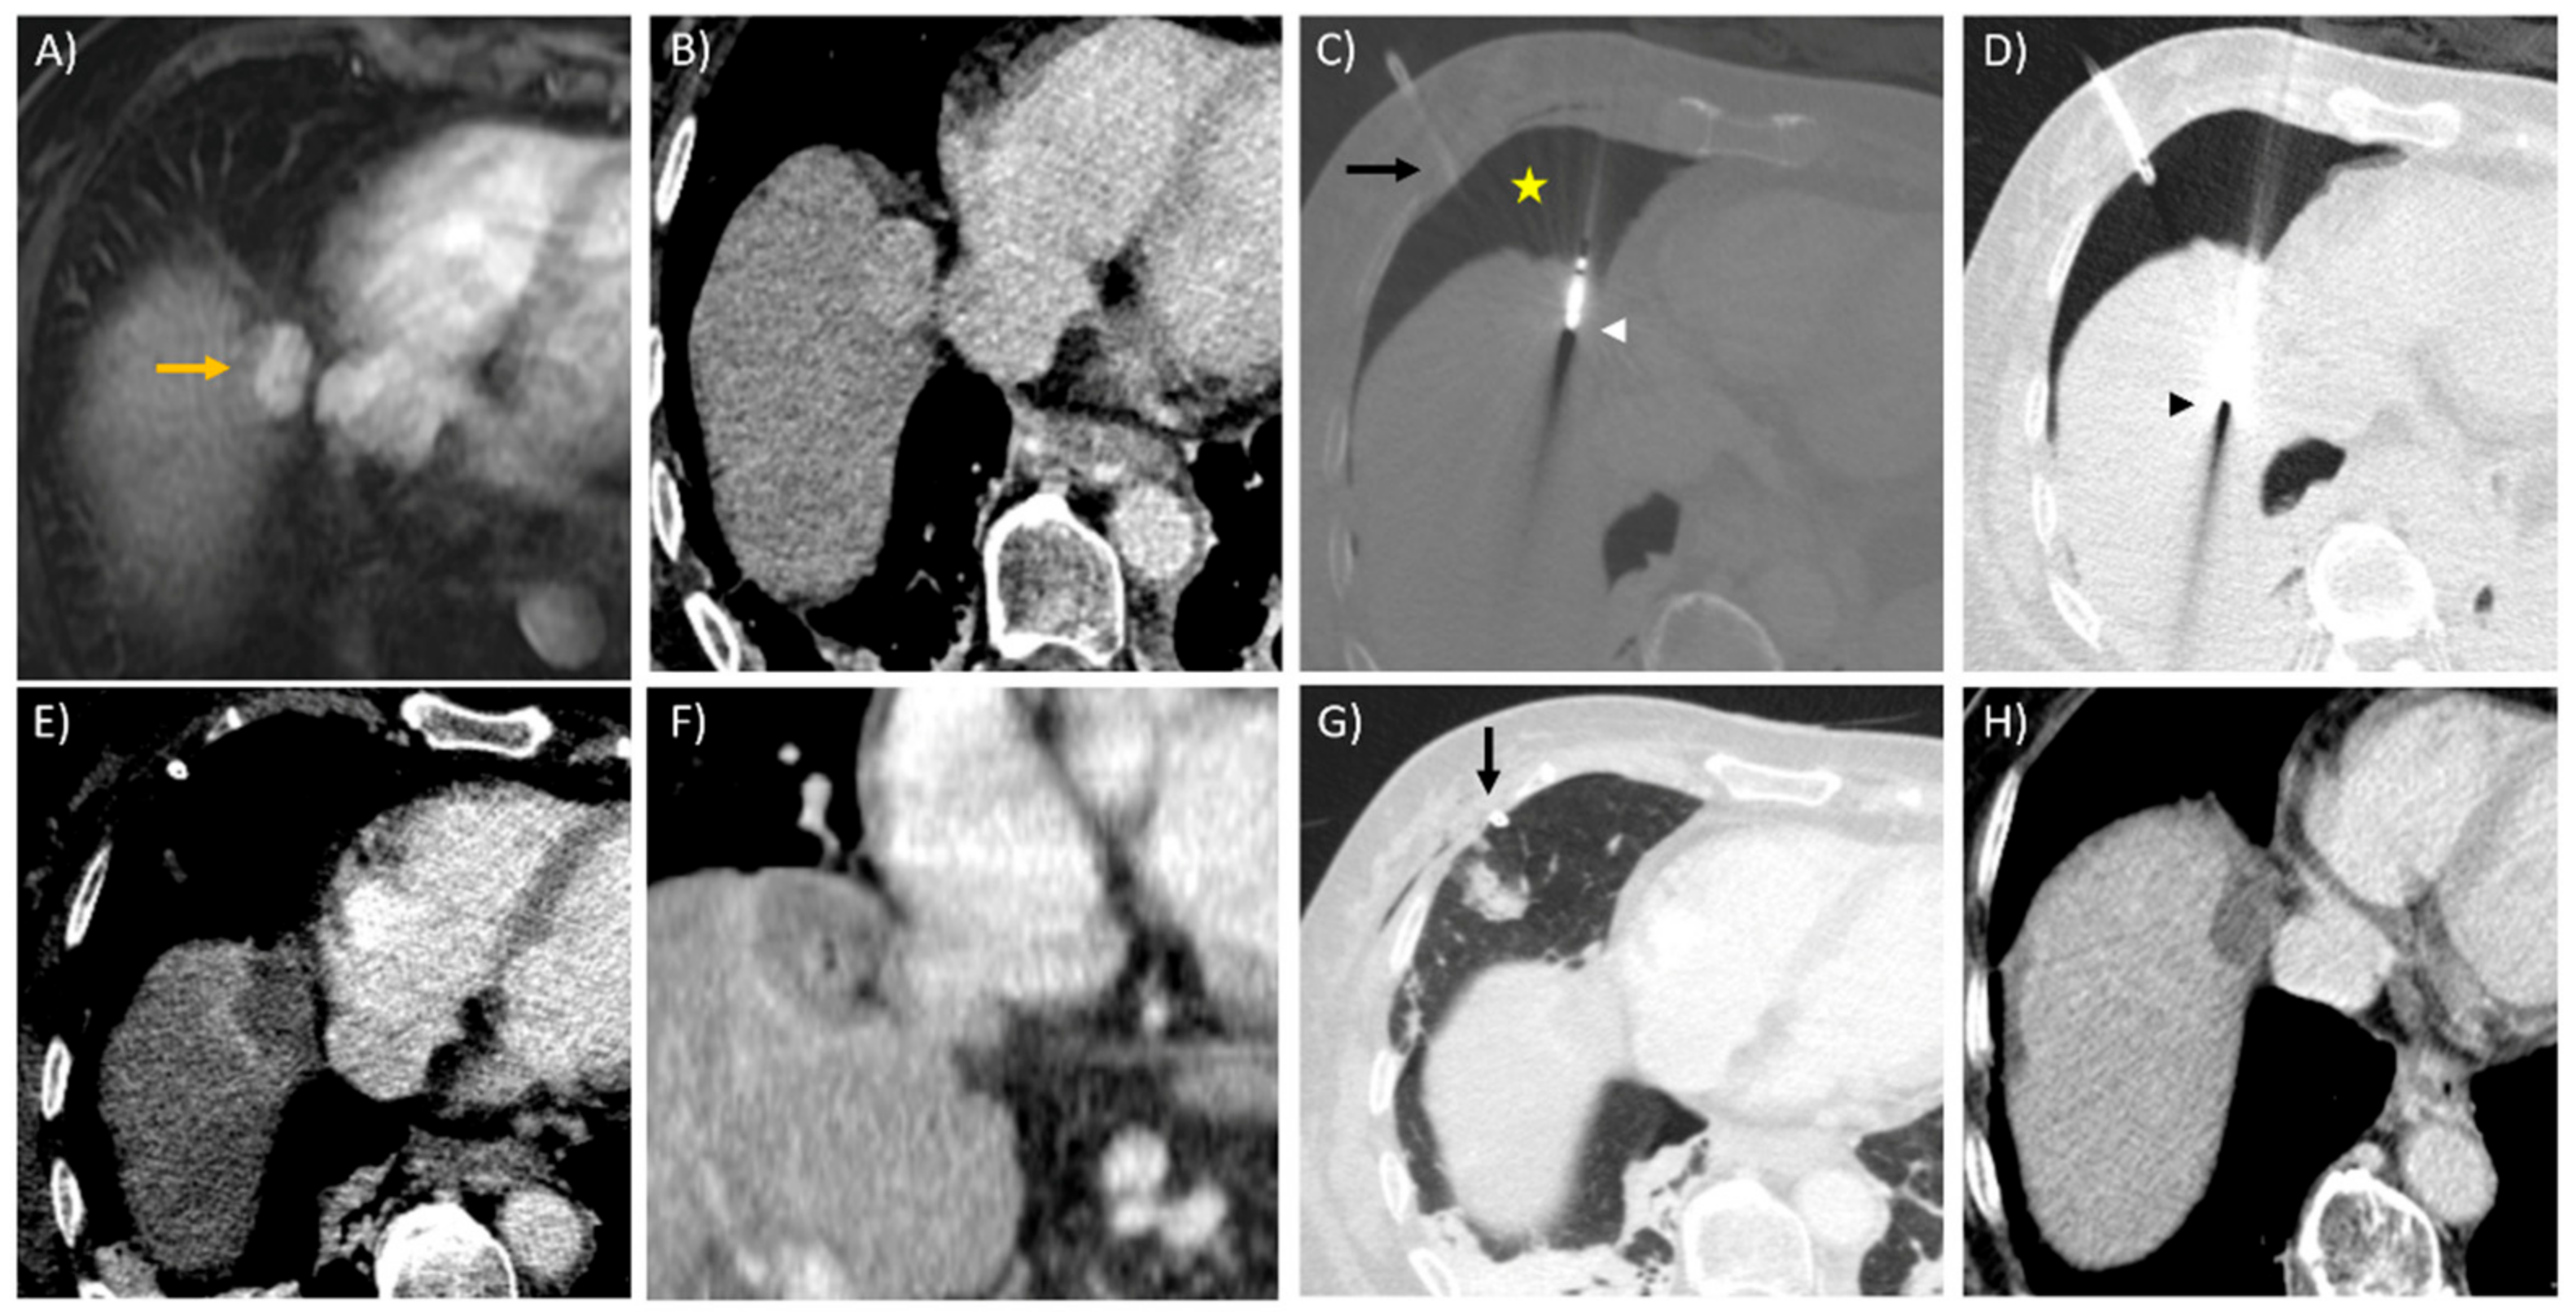

- Asvadi, N.H.; Anvari, A.; Uppot, R.N.; Thabet, A.; Zhu, A.X.; Arellano, R.S. CT-Guided Percutaneous Microwave Ablation of Tumors in the Hepatic Dome: Assessment of Efficacy and Safety. J. Vasc. Interv. Radiol. 2016, 27, 496–502. [Google Scholar] [CrossRef]

- Schaible, J.; Lürken, L.; Wiggermann, P.; Verloh, N.; Einspieler, I.; Zeman, F.; Schreyer, A.G.; Bale, R.; Stroszczynski, C.; Beyer, L. Primary efficacy of percutaneous microwave ablation of malignant liver tumors: Comparison of stereotactic and conventional manual guidance. Sci. Rep. 2020, 10, 18835. [Google Scholar] [CrossRef] [PubMed]

- Engstrand, J.; Toporek, G.; Harbut, P.; Jonas, E.; Nilsson, H.; Freedman, J. Stereotactic CT-Guided Percutaneous Microwave Ablation of Liver Tumors With the Use of High-Frequency Jet Ventilation: An Accuracy and Procedural Safety Study. Am. J. Roentgenol. 2017, 208, 193–200. [Google Scholar] [CrossRef]

- Kambadakone, A.; Baliyan, V.; Kordbacheh, H.; Uppot, R.N.; Thabet, A.; Gervais, D.A.; Arellano, R.S. Imaging guided percutaneous interventions in hepatic dome lesions: Tips and tricks. World J. Hepatol. 2017, 9, 840–849. [Google Scholar] [CrossRef]

- Rhim, H.; Lim, H.K. Radiofrequency ablation for hepatocellular carcinoma abutting the diaphragm: The value of artificial ascites. Abdom. Imaging 2008, 34, 371–380. [Google Scholar] [CrossRef]

- Rhim, H.; Lim, H.K.; Kim, Y.-S.; Choi, N. Percutaneous Radiofrequency Ablation with Artificial Ascites for Hepatocellular Carcinoma in the Hepatic Dome: Initial Experience. Am. J. Roentgenol. 2008, 190, 91–98. [Google Scholar] [CrossRef]

- Smolock, A.R.; Lubner, M.G.; Ziemlewicz, T.J.; Hinshaw, J.L.; Kitchin, D.R.; Brace, C.L.; Lee, F.T. Microwave ablation of hepatic tumors abutting the diaphragm is safe and effective. Am. J. Roentgenol. 2015, 204, 197–203. [Google Scholar] [CrossRef] [PubMed]

- De Baère, T.; Dromain, C.; Lapeyre, M.; Briggs, P.; Duret, J.S.; Hakime, A. Artificially induced pneumothorax for percutaneous transthoracic radiofrequency ablation of tumors in the hepatic dome: Initial experience. Radiology 2005, 236, 666–670. [Google Scholar] [CrossRef] [PubMed]